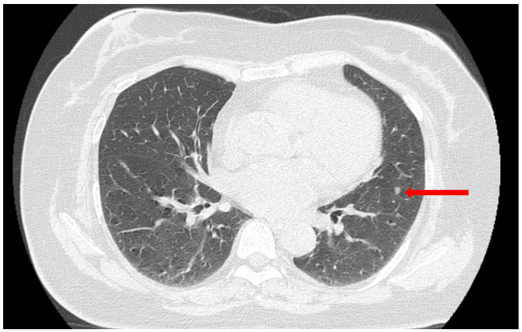

Cắt lớp vi tính (CT) lồng ngực (07/2024):

Hình ảnh thùy dưới phổi trái sát rãnh liên thùy có 02 nốt đặc, đường kính 4 mm và 4,5 mm, bờ tròn đều.

CT ngực: Hìn ảnh hai nốt đặc 4–4,5 mm không thay đổi so với07/2024.